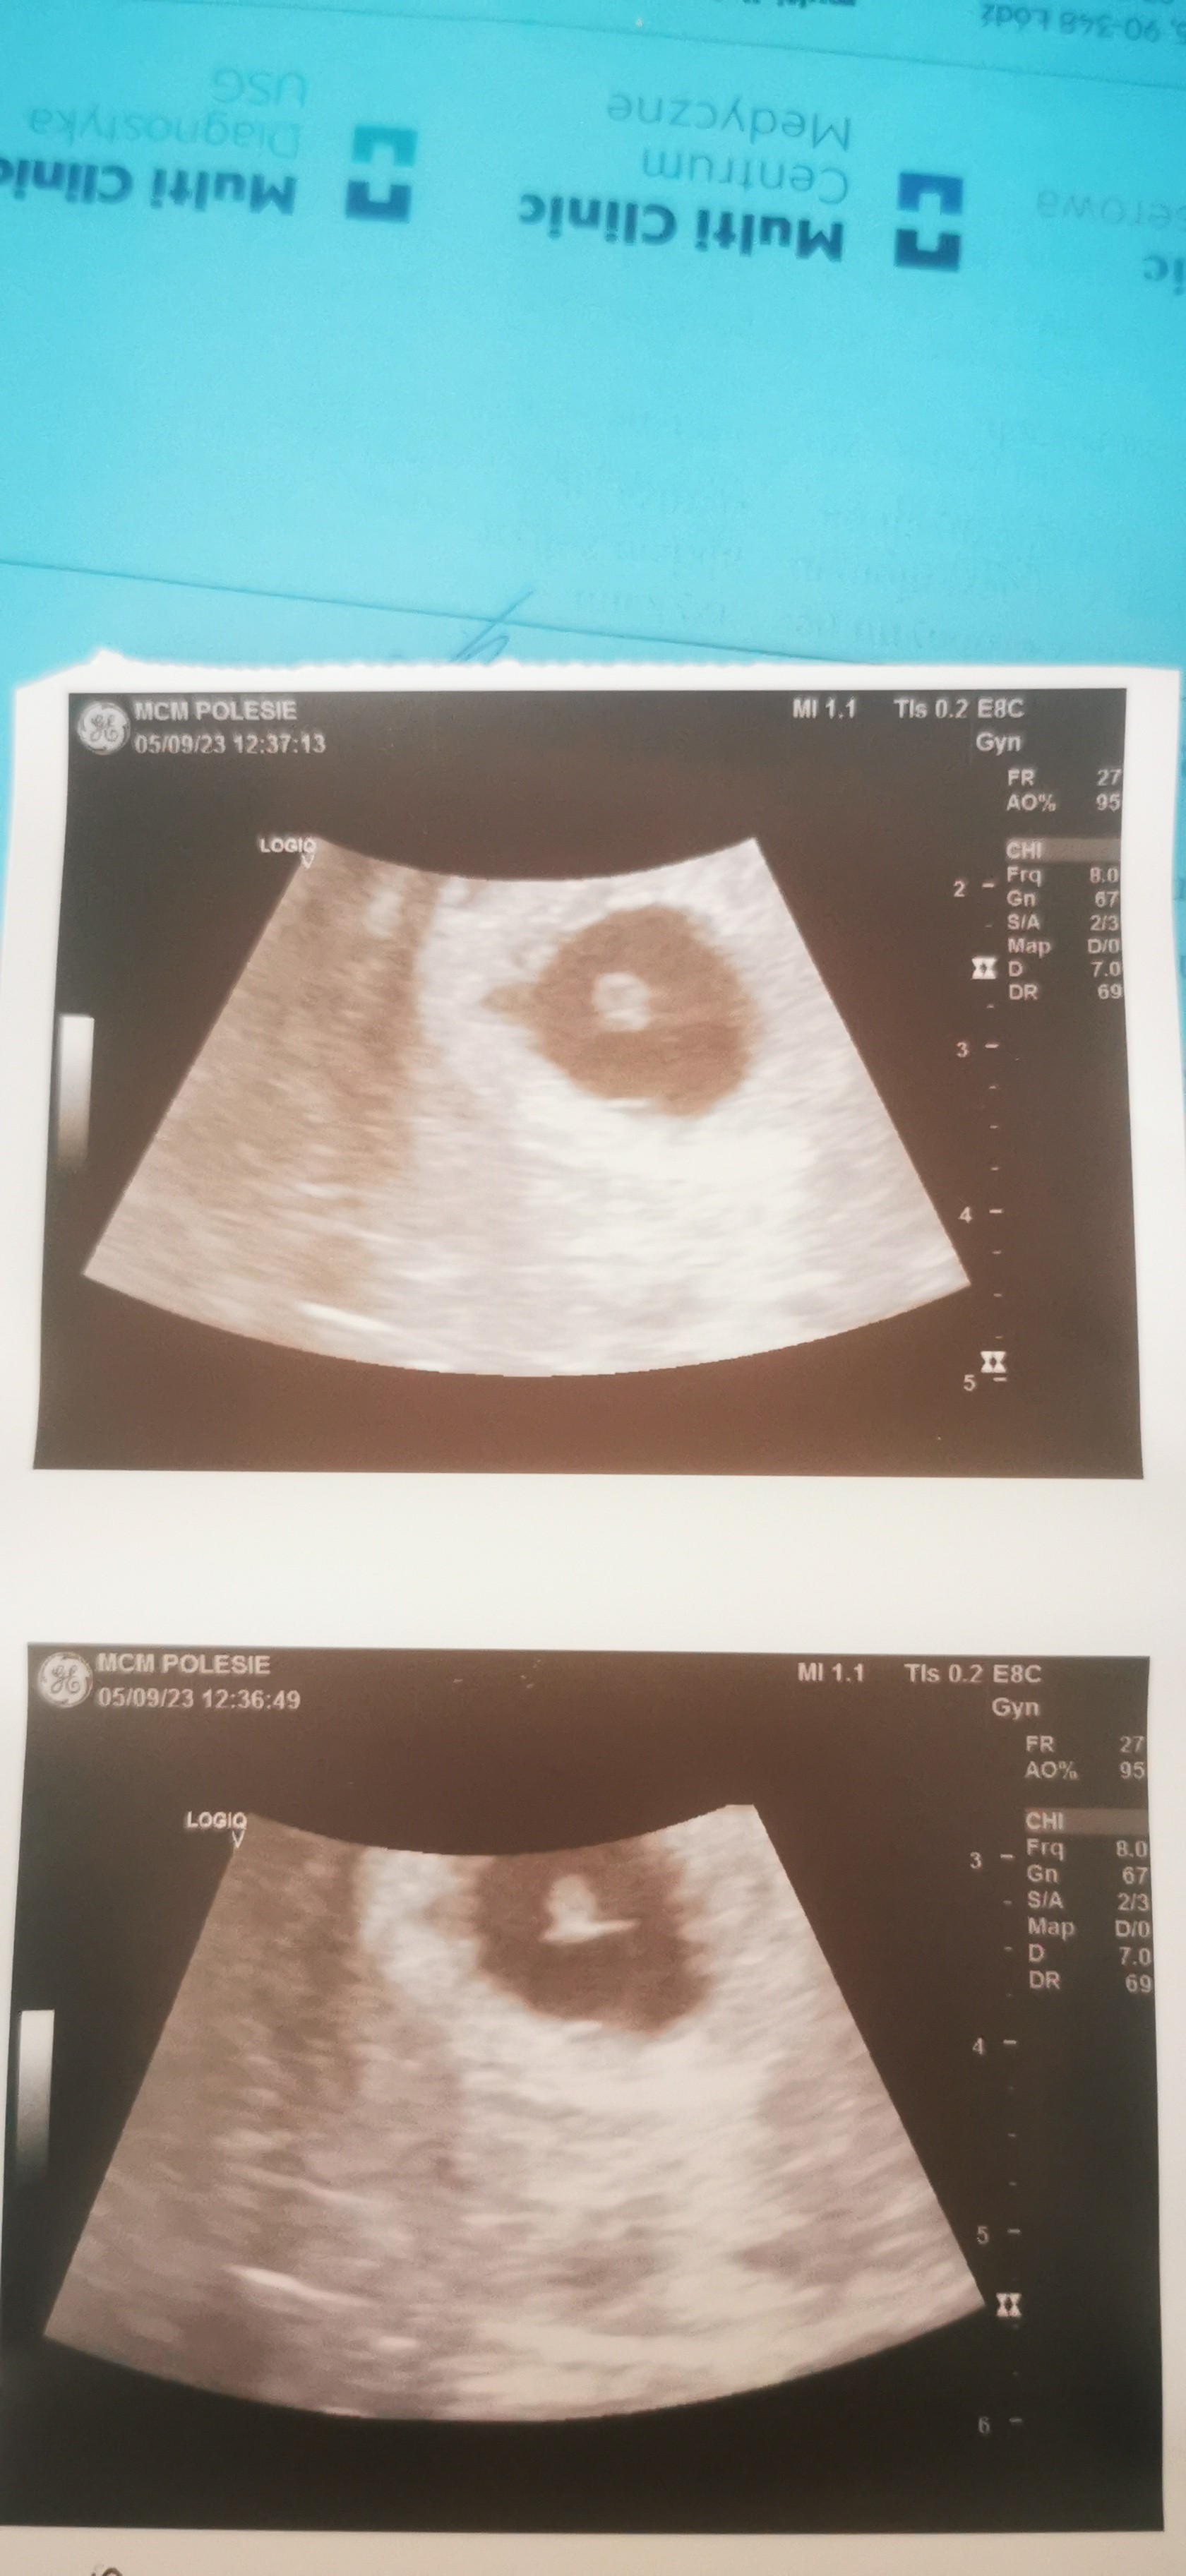

Ja właśnie jestem po lekarzu, karty ciąży nadal mi nie założyła bo nie jest pewna czy ciąża rozwija się prawidłowo.

Mam dosyć tej kobiety na jutro prywatnie się zapisałam

Załączniki

• IMG_20230905_110610.jpg

IMG_20230905_110610.jpg

734,3 KB · Wyświetleń: 98